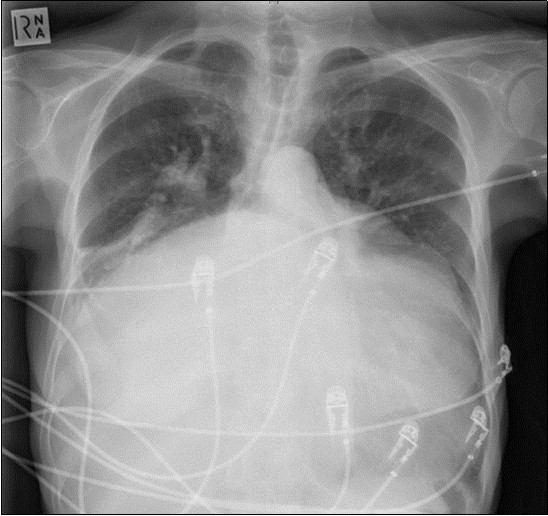

A 64-year-old woman was admitted to the Intensive Care Unit (ICU) after a medical emergency team (MET) call from the cardiology ward due to a reduced level of consciousness and respiratory distress. Past medical history included rheumatic fever as a child and chronic atrial fibrillation. She had been admitted to hospital 3 days previously with worsening shortness of breath. On observation she was drowsy but rousable to voice, with a respiratory rate of thirty breaths per minute. Examination revealed a raised jugular venous pressure, a pan-systolic murmur as well as a long mid-diastolic murmur, both loudest at the apex and radiating to the axilla, a soft first heart sound, a displaced tapping apex beat, and bi-basal medium-intensity inspiratory crepitations. Her electrocardiogram showed atrial fibrillation with a rapid ventricular response of 126 beats per minute. Her arterial blood gas demonstrated an acute on chronic respiratory acidosis with a pH 7.02, PaCO2 176 mmHg, and a HCO3- of 43 mmol/L. An antero-posterior (AP) chest x-ray on admission displayed cardiomegaly, splayed carina and hilar venous congestion, with a lateral film showing the left atrium occupying a significant part of the chest cavity (see Figure 1a, Figure 1b).

Figure 1a.Chest X-ray Antero-posterior view. Findings showing enlarged left atrium, splaying of the carina, hilar venous congestion